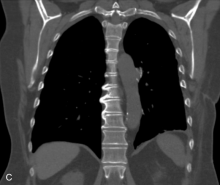

A 68-year-old woman presented to the thoracic surgery clinic for evaluation of a large left lower lobe mass. Six months prior, she had undergone attempted right-heart-catheterization at an outside hospital, which was aborted due to an acute pulmonary hemorrhage. Physical examination revealed decreased breath sounds at the left lung base. Computed tomography revealed an enhancing 8.9 cm mass (Figure 1A, arrow)arising from the left lower lobe segmental pulmonary artery (Figure 1B, arrowhead), compatible with a pseudoaneurysm. Iatrogenic damage to the pulmonary artery and its branches is a known complication of percutaneous interventional procedures, such as Swan-Ganz catheterization (1).

Small pseudoaneurysms can frequently bemanaged with a transcatheter approach utilizing coil-embolization or thrombin injection. However, larger lesions may require surgical intervention (2). The patient underwent left thoracotomy and left lower lobectomy. She was seen in the clinic following hospital discharge and was recovering well without complications (Figure 2).